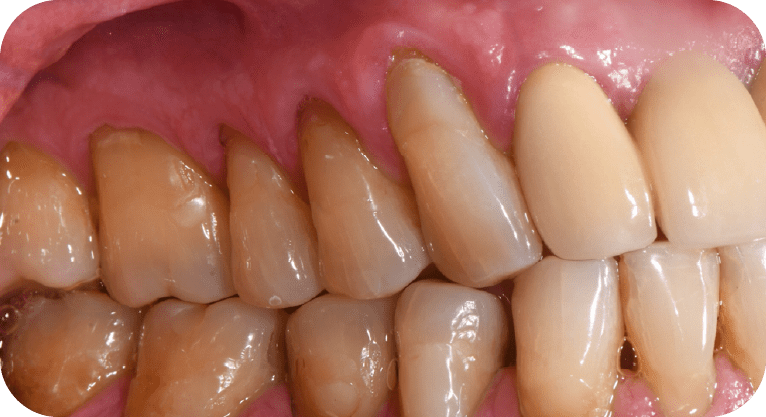

Paciente masculino, “65” años

Tratamiento: Cirugía de encías

El paciente presentaba sensibilidad dental causada por la exposición de los cuellos dentales, por lo que se realizó una cirugía de recubrimiento radicular con injerto gingival y reposicionamiento de encía, logrando

proteger las raíces expuestas, reducir la hipersensibilidad y mejorar tanto la función como la estética periodontal, con resultados satisfactorios para el paciente.